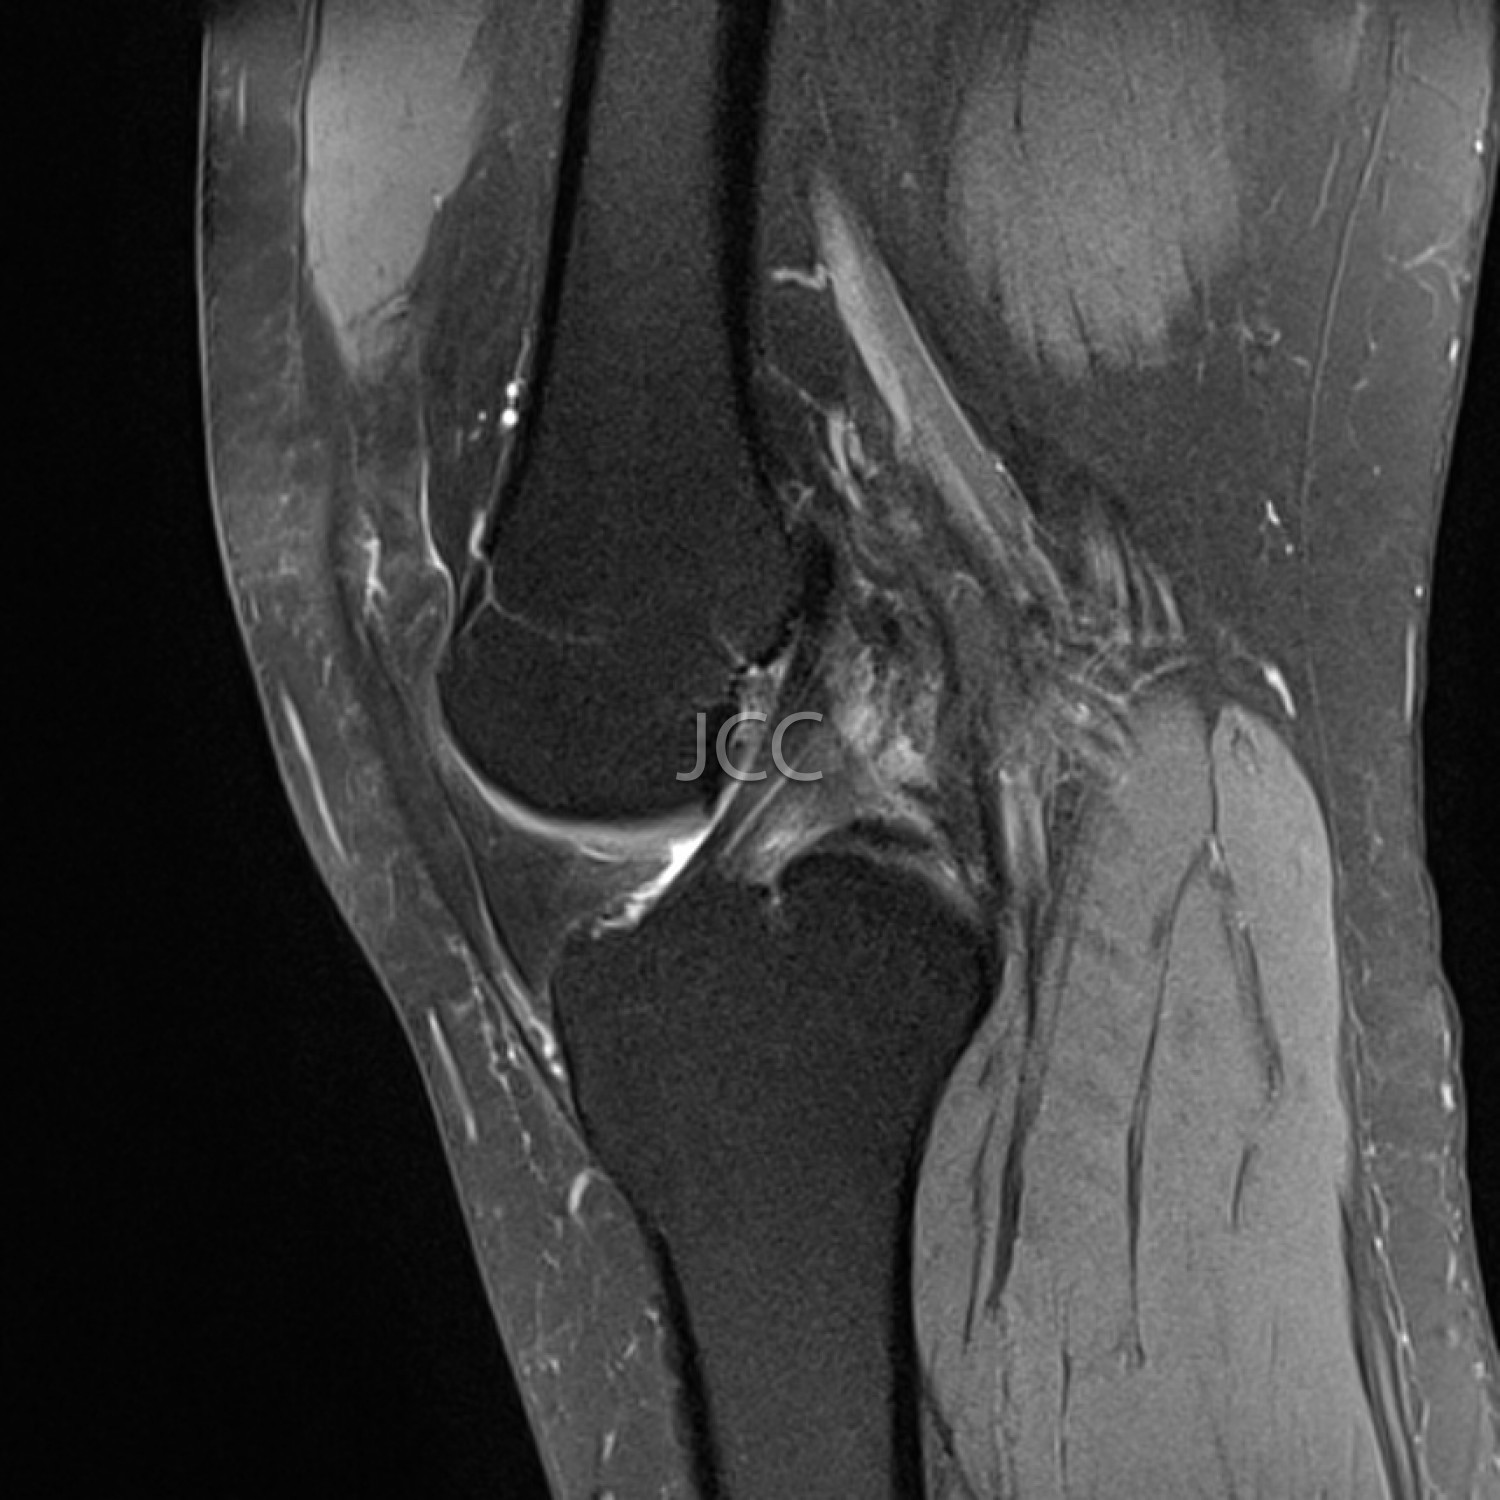

Ressonância Magnética de Alto Campo - RM Osteo-Articular

A Ressonância Magnética de Alto Campo é uma técnica de imagem que não utiliza radiação baseando-se num campo magnético e ondas de radiofrequência para estudar detalhadamente os órgãos do corpo humano.

Atualmente, com os equipamentos mais modernos de 1.5 e 3 TESLA é possível não só estudar cérebro, coluna e articulações constituindo, também, a técnica de eleição para avaliação vascular, coração, fígado e pâncreas.